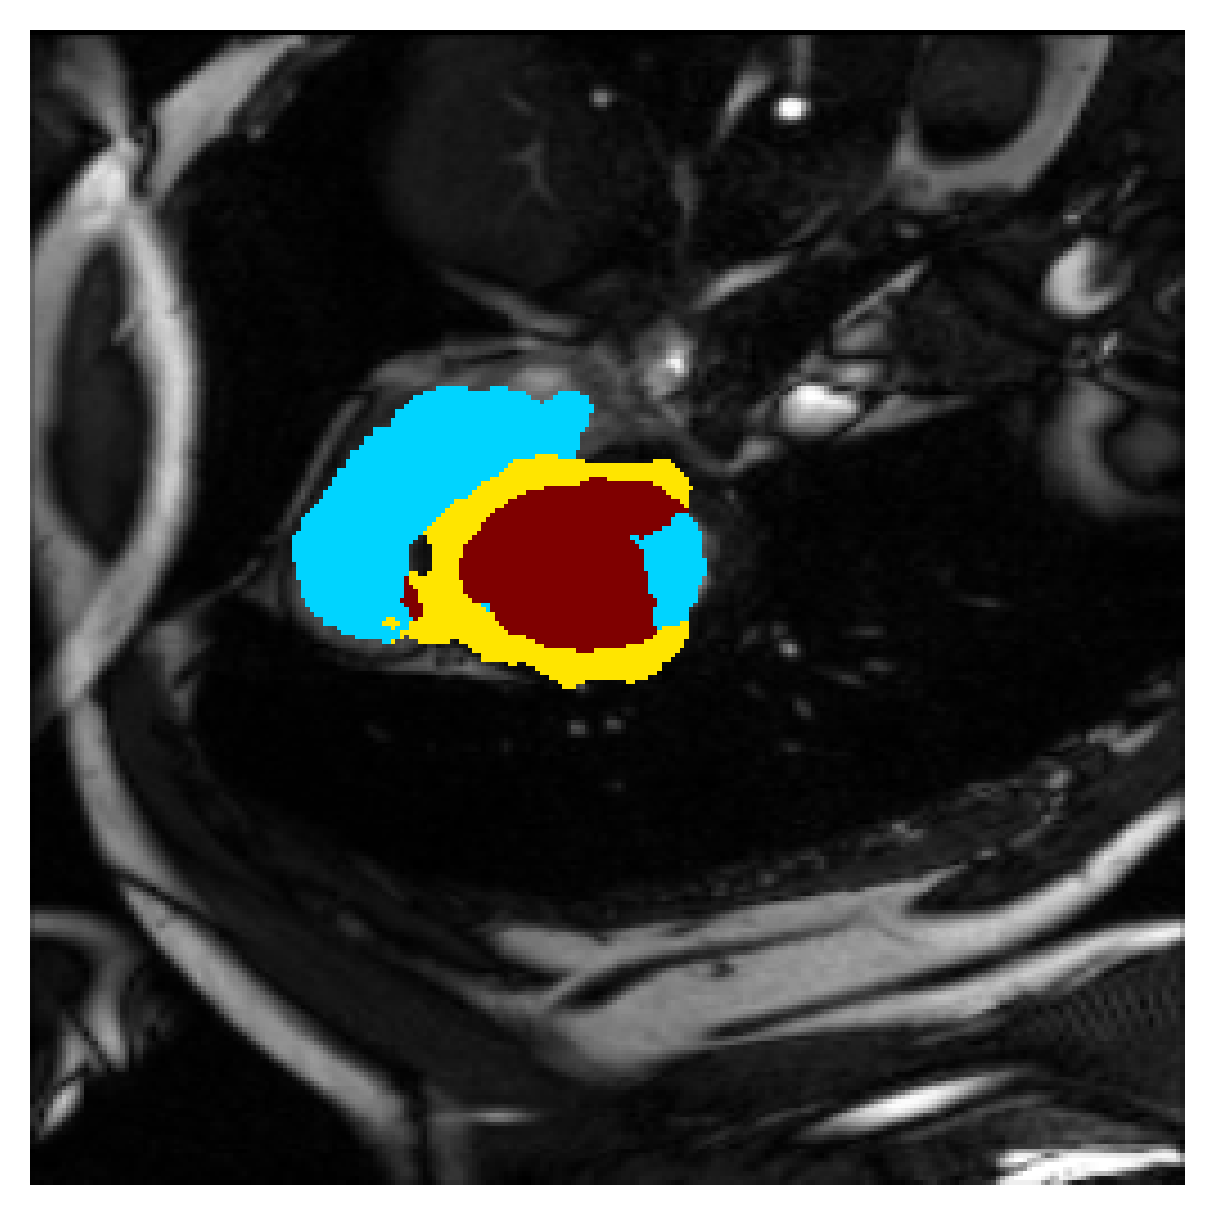

Qualitative comparison

In Figure 6 we provide qualitative results on a number of randomly chosen test set slices. Upon visual inspection, we can observe that training with the intensity-aware distances (particularly with and ) follows the image gradients better and is better at recovering the underlying shape than the Euclidean version. The CRF-loss seems to recover the shape of the myocardium and left ventricle to some extent, but fails entirely on the right ventricle.